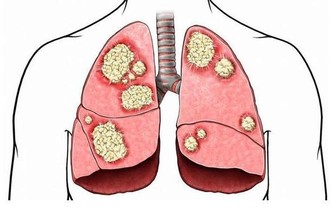

下面,就為大家說說那些隱匿的肝病信號。

(4)牙齦和鼻子出血

很多人都經歷過牙齦流血,或者鼻子出血,如果是頻繁出血,而且量大又止不住血,就要警惕肝病。

當肝細胞損傷後,肝臟產生凝血因子的功能下降,凝血機制就會發生障礙。

肝病患者的出血,可能是刷牙時牙齦出血,或者活動鼻子時出血,也可能是吃東西時,食物上出現血痕。

肝病越嚴重,出血現象越嚴重。